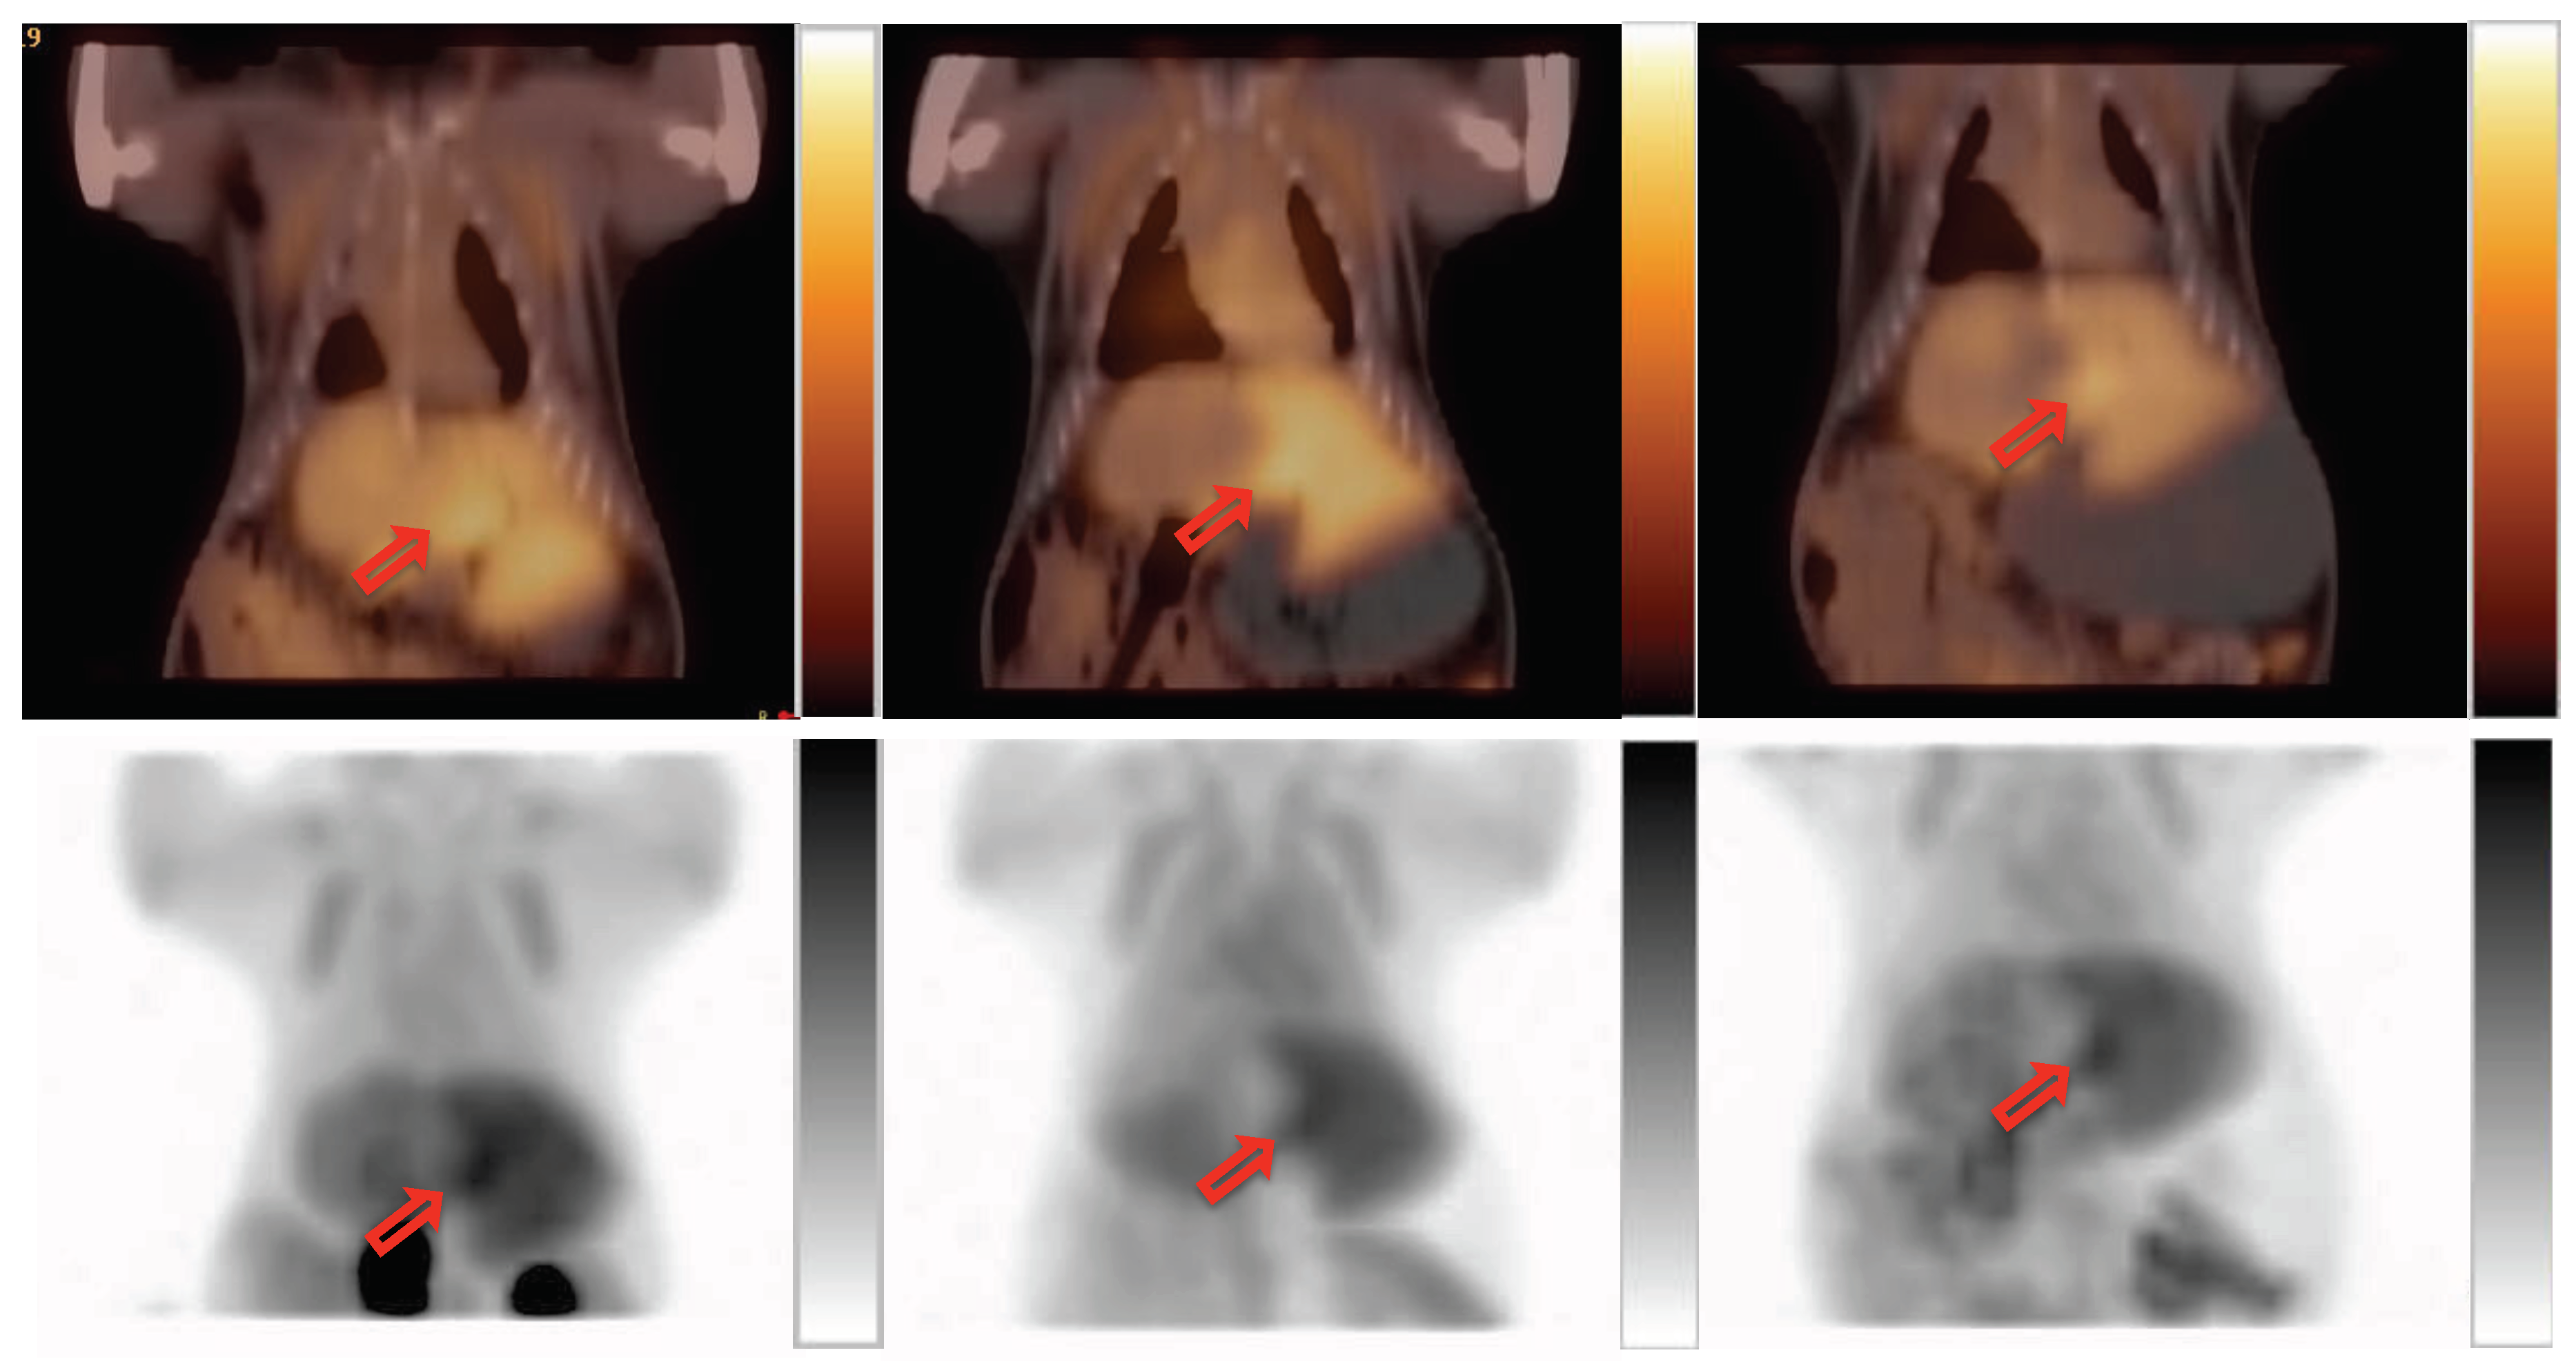

2.2. PET Imaging